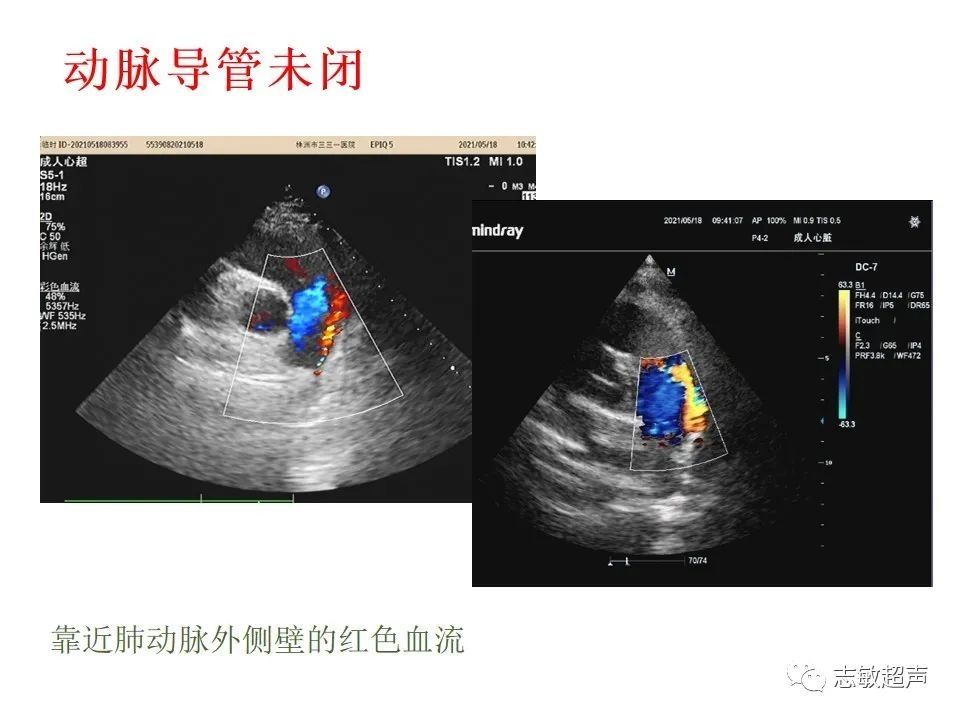

3.动脉导管未闭